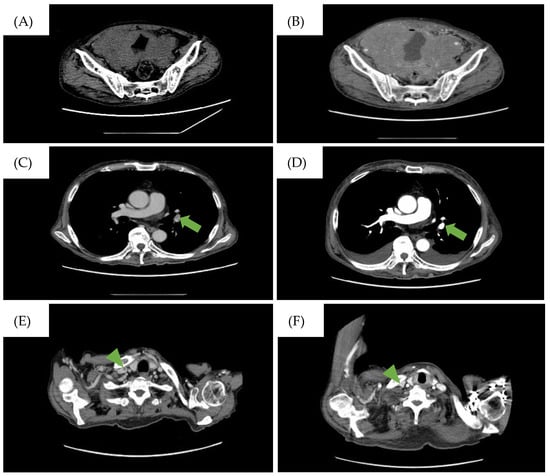

2. Case Presentation